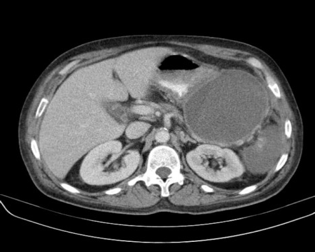

CT Scan can provide a more detailed image than ultrasound